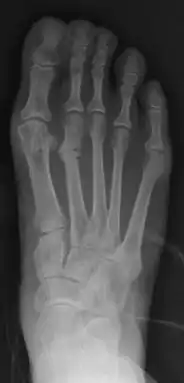

Primus varus deformity is the leaning of the first metatarsal bone away from the second metatarsal and towards the opposite foot (Fig. 1). As it leans over, its head sticks out to form the bunion bump and it also widens the forefoot to cause shoes feeling too tight. Thus when bunion pain becomes unmanageable, surgical correction is to narrow the forefoot by repositioning of the first metatarsal head back to its normal position. This can be done by osteotomy (bone-breaking), soft tissue (non-osteotomy) or fusion techniques.

Syndesmosis procedure addresses specifically the two fundamental problems of metatarsus primus varus deformity that gives rise to the bunion deformity. They are leaning and instability of the first metatarsal bone . Syndesmosis procedure uprights the leaning first metatarsal bone with strong binding sutures between it and the second metatarsal bone (Fig. 2) and then also stabilizes it uniquely by creating a fibrous connecting bridge between these two bones (Fig. 3, 4). First metatarsal bone can be readily realigned because by definition of the metatarsus primus varus deformity its first metatarsal is abnormally loose and mobile.